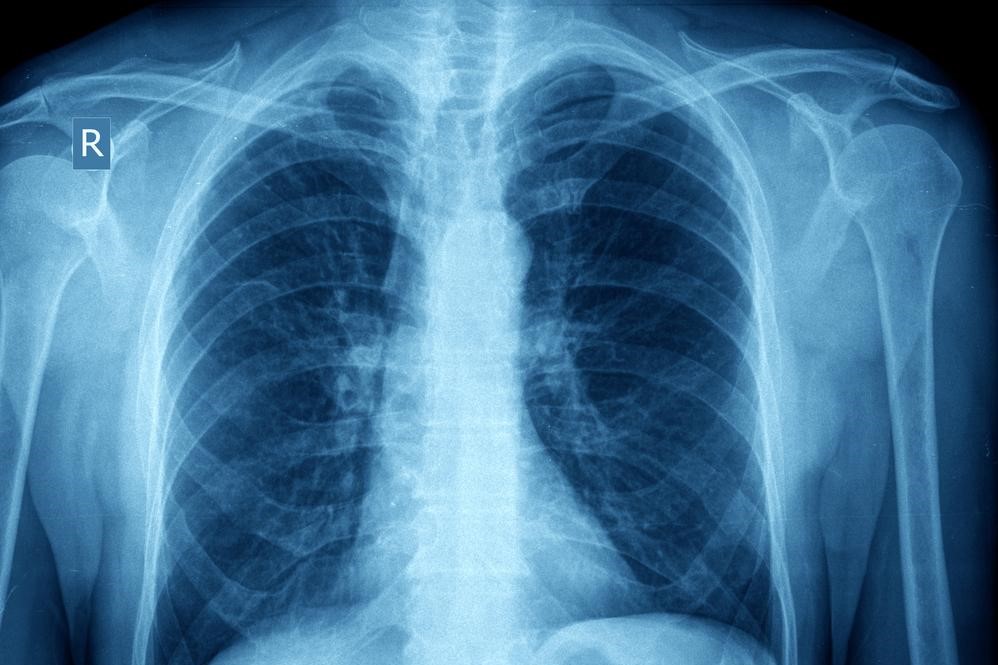

It is believed that patients always have some degree of inflammation in the lungs that make them more sensitive triggers. Chronic inflammation over time can lead to changes in the structures of the lungs and increased mucous production. Proper control of asthma can limit these effects.